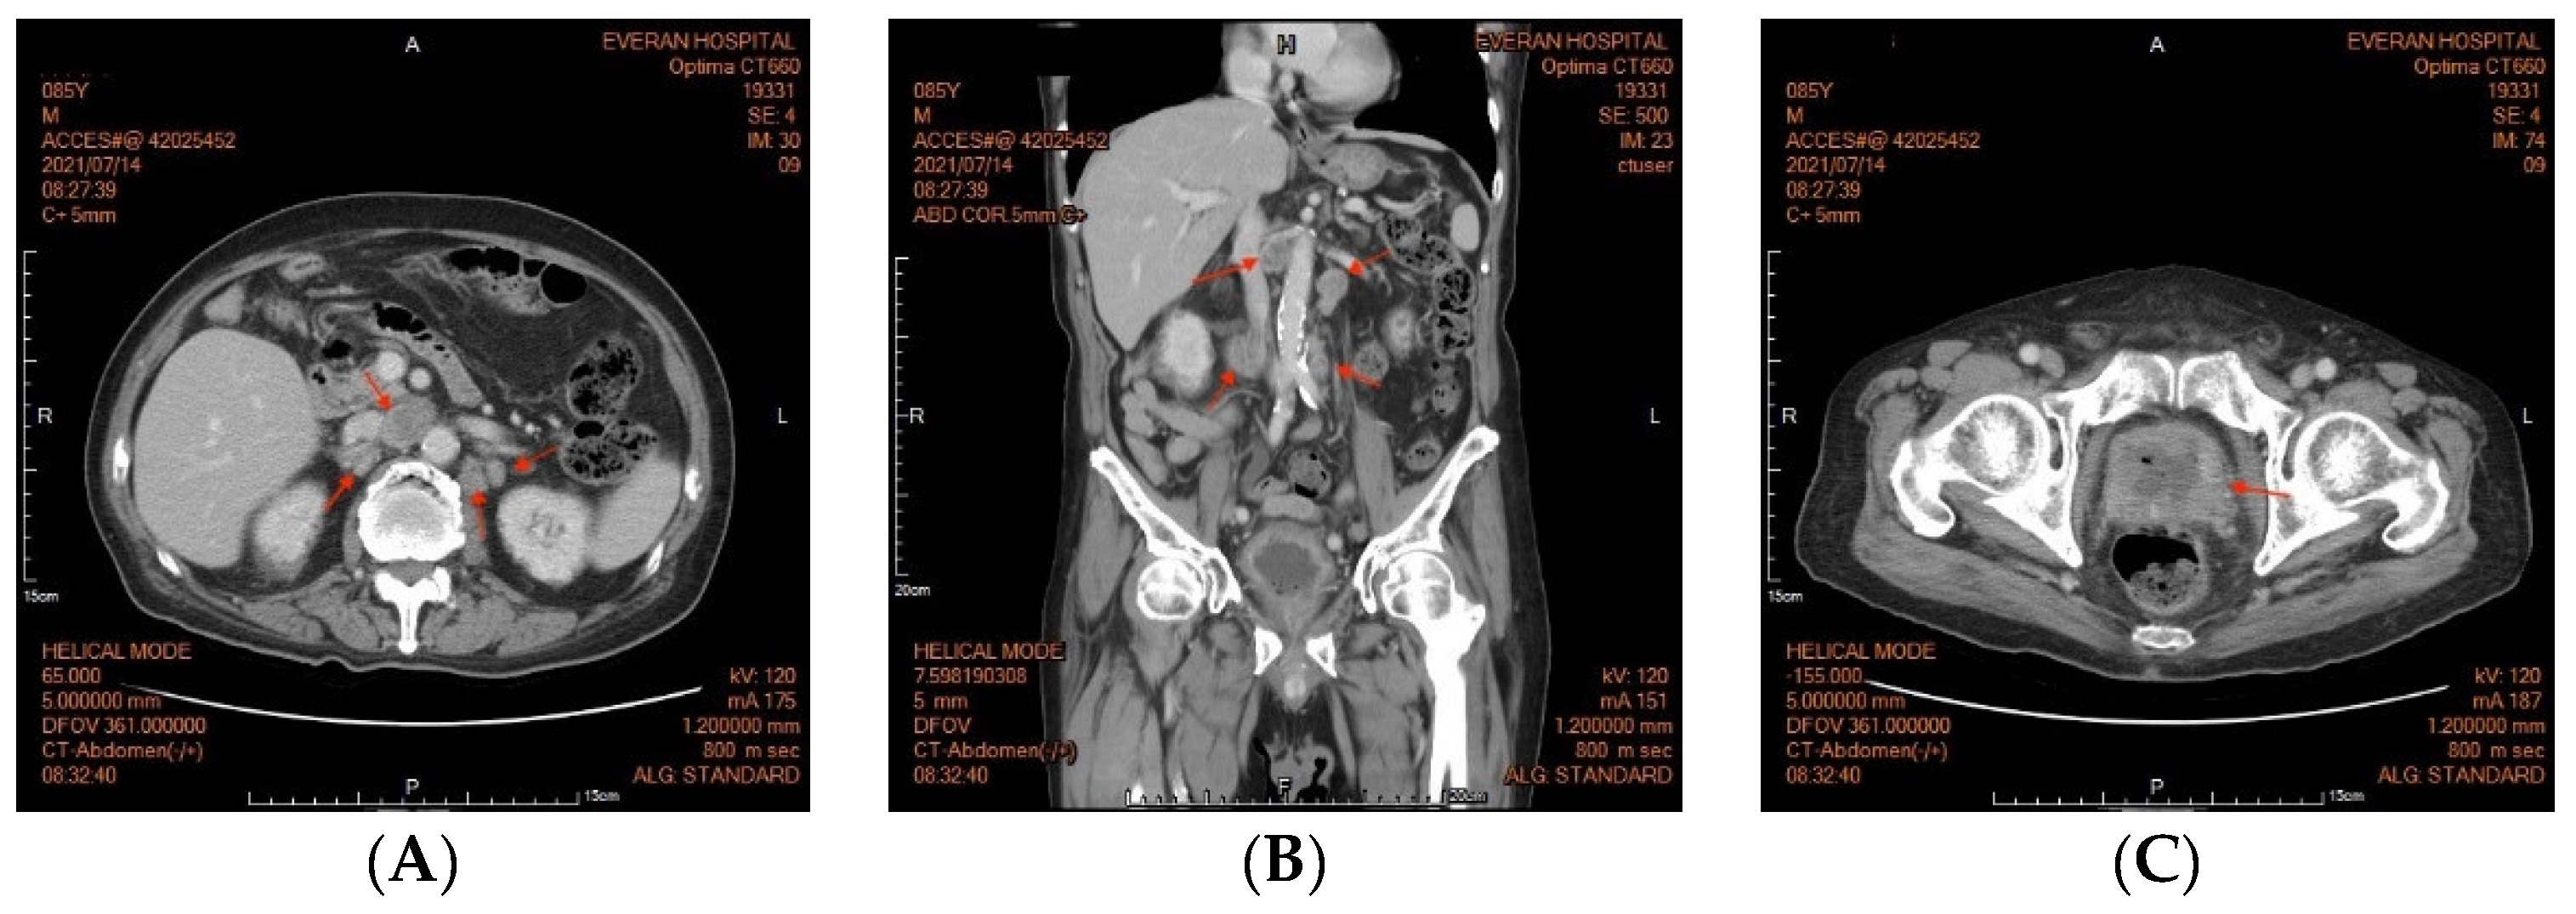

An 85-year-old male patient presented with a history of diabetic nephropathy and benign prostate hyperplasia (BPH) with lower urinary tract symptoms (LUTS) under oral alfa-blocker treatment. He was a non-smoker and had no family history of prostate cancer. His initial PSA level was 4.2 ng/dL, and transrectal ultrasonography showed that his prostate was 60 g in weight on 3 April 2019. He underwent PAE by a cardiologist on 18 April 2019, after an outpatient visit for hypertension. His PSA level decreased to 1.6 ng/dL one month later, but then gradually increased to 2.83 ng/dL three months later and 2.91 ng/dL five months later (29 October 2019). He underwent transrectal ultrasonography again six months postoperatively, which showed that his prostate weighed 23 g. He was then lost to follow-up until 2021. He returned to our outpatient clinic on account of dysuria, urge incontinence and perineal discomfort in March 2021. As pyuria was found in a urine routine test, he was treated with antibiotics initially. His PSA level was 15.41 in March 2021. He did not respond well to oral medications for LUTS, and he was then referred to urologic outpatient services due to acute urinary retention on May 18th. His serum PSA level was 12.58 ng/dL, and an echogram showed a prostate weight of 97 g. A digital rectal examination (DRE) revealed a firm prostate with an irregular surface, and malignancy of the prostate was highly suspected. We then performed a transrectal prostate biopsy and TURP on 29 June 2021. The intraoperative findings were a papillary lesion at the surface of necrotic tissue at the transition zone, and the total resected chips weighed 61 g. The pathology report eventually showed adenocarcinoma, Gleason score 5 + 5 = 10 (>5%). An abdominal computed tomography revealed multiple lymph node metastases at the paraaortic area (Figure 1), and a bone scan revealed boney metastasis at the L-spine (Figure 2). The clinical stage was cT2cN1M1b. He was then treated with regular hormone therapy. The last checked PSA value was 1.5 ng/dL on 15 June 2022. Written informed consent was obtained from the patient for the publication of this case report.

Figure 1.

(A) Abdominal computed tomography (CT) revealed multiple lymph node enlargement at the paraaortic area (arrowhead). (B) Sagittal view of the abdomen CT. (C) Abdominal CT of the pelvis revealed a prostate gland with heterogenous density.